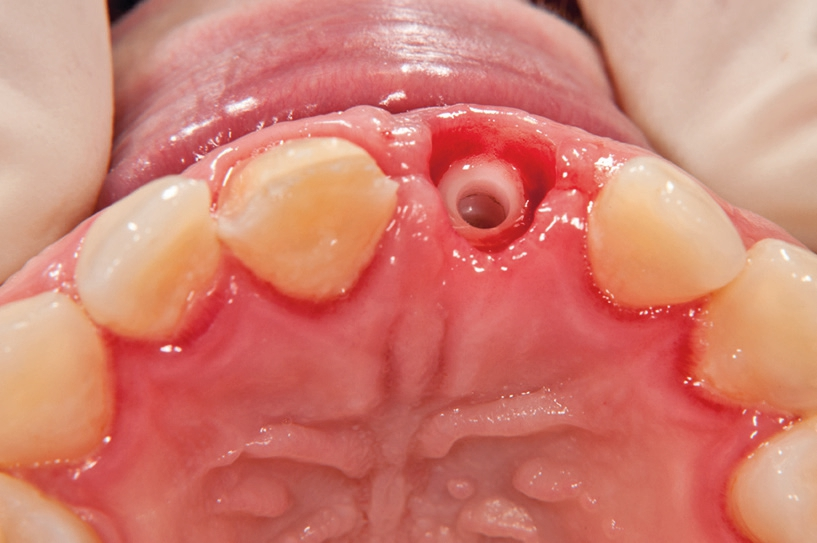

Gleichzeitig mit der prothetischen Versorgung des Implantats wurde auch für Zahn 11 ein Veneer geplant. Zum Einsatz kam ein Zeramex T Implantat Durchmesser 5,5 mm, Länge 12 mm. Für die Kronenversorgung wurde ein mit e. Max überpresstes CAD-Abutment gewählt. Während der Einheilphase des Implantats kam eine Sunflex-Prothese zum Einsatz.